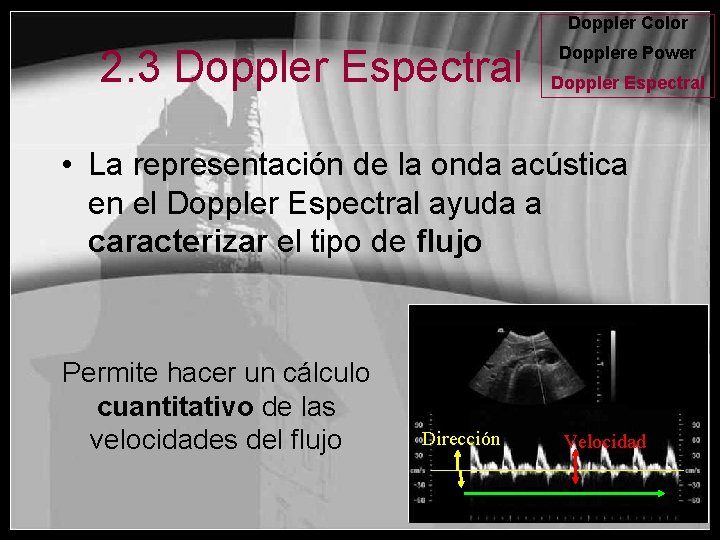

Doppler Color 2. 3 Doppler Espectral Dopplere Power Doppler Espectral • La representación de la onda acústica en el Doppler Espectral ayuda a caracterizar el tipo de flujo Permite hacer un cálculo cuantitativo de las velocidades del flujo Dirección Velocidad